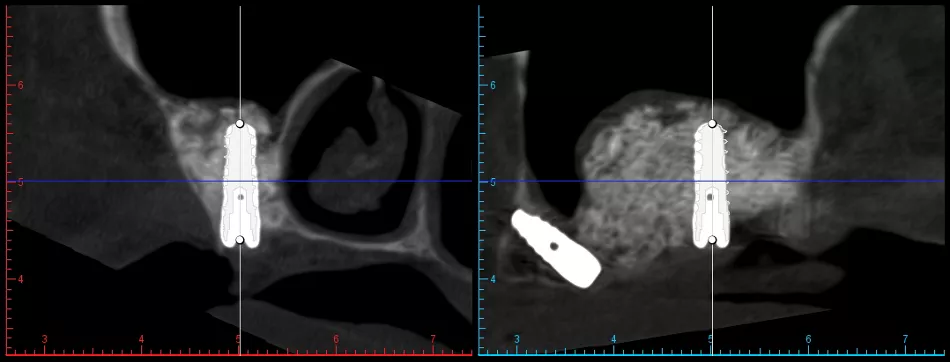

Figs. 33-35 From left to right: Sagittal view in coDiagnostiX® showing planned placement of a Straumann® BLX Ø4.0 x 12 mm implant in the maxillary sinus, corresponding sagittal CBCT slice confirming anatomical positioning, and detailed view of the BLX implant macrogeometry (Straumann®, SLActive® surface, TorcFit™ connection).

Figs. 36-38 From left to right: Sagittal view in coDiagnostiX® showing planned placement of a Straumann® BLC Ø3.5 x 12 mm implant in the anterior maxilla, corresponding sagittal CBCT slice confirming bone availability and positioning, and detailed view of the BLC implant macrogeometry (Straumann®, SLActive® surface, TorcFit™ connection).

Figs. 40,41 From left to right: Sagittal view in coDiagnostiX® showing planned placement of a Straumann® BLX Ø4.0 x 12 mm implant in the maxillary tuberosity, corresponding sagittal CBCT slice confirming anatomical positioning.

Figs. 42,43 Note the importance of a less aggressive thread design in proximity to the anterior wall of the maxillary sinus and the lateral nasal plate. This design helps minimize the risk of perforation and enhances implant stability in anatomically delicate areas.